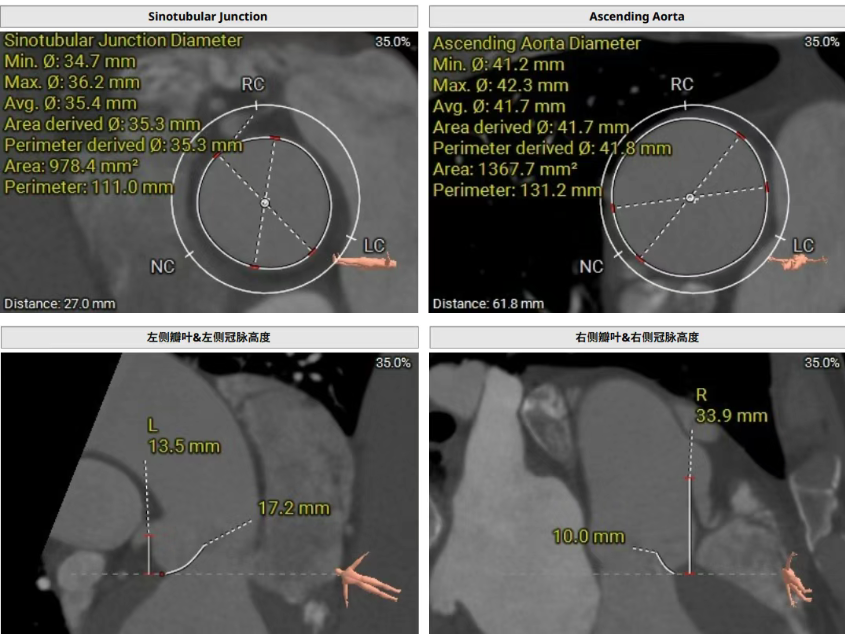

術前CT評估提示,患者主動脈瓣為三葉瓣,瓣葉增厚。舒張期可見右冠瓣脫垂,右冠瓣瓣葉輕度鈣化。存在三個瓣竇,分佈較為均勻。主動脈瓣環周長折算直徑為28.0 mm;左心室流出道(LVOT)周長折算直徑為29.5 mm,未見鈣化及狹窄。主動脈竇管交界(STJ)直徑為35.3 mm,升主動脈直徑為41.8 mm。冠狀動脈開口高度如下:左冠狀動脈(LCA)13.5 mm,瓣葉長度17.2 mm;右冠狀動脈(RCA)33.9 mm,瓣葉長度10.0 mm。左側冠狀動脈見輕度鈣化。心臟呈橫位心,左心室與主動脈夾角為135°。